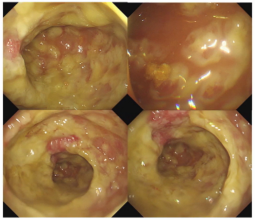

·  腸鏡檢查

直腸和降結(jié)腸散在黏膜充血、水腫、淺表糜爛,病灶間黏膜基本正常,全部有黃白色苔樣偽膜,其形狀為斑片狀或地圖狀,不易剝離。